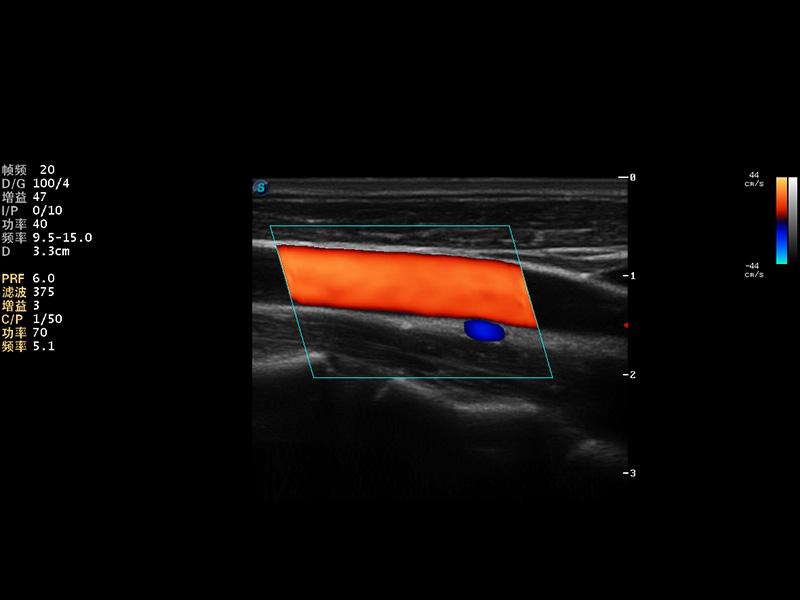

S9便携式彩色多普勒超声诊断仪是新葡的京集团8814检测站研发的高端便携彩超设备,外观设计新颖、产品性能卓越。S9在便携超声领域采用了突破传统的触摸屏交互设计,并以先进的软件硬件技术和设计理念,为您带来清晰的图像质量、稳定的工作性能和便捷的操作体验。

AutoC智能血流追踪